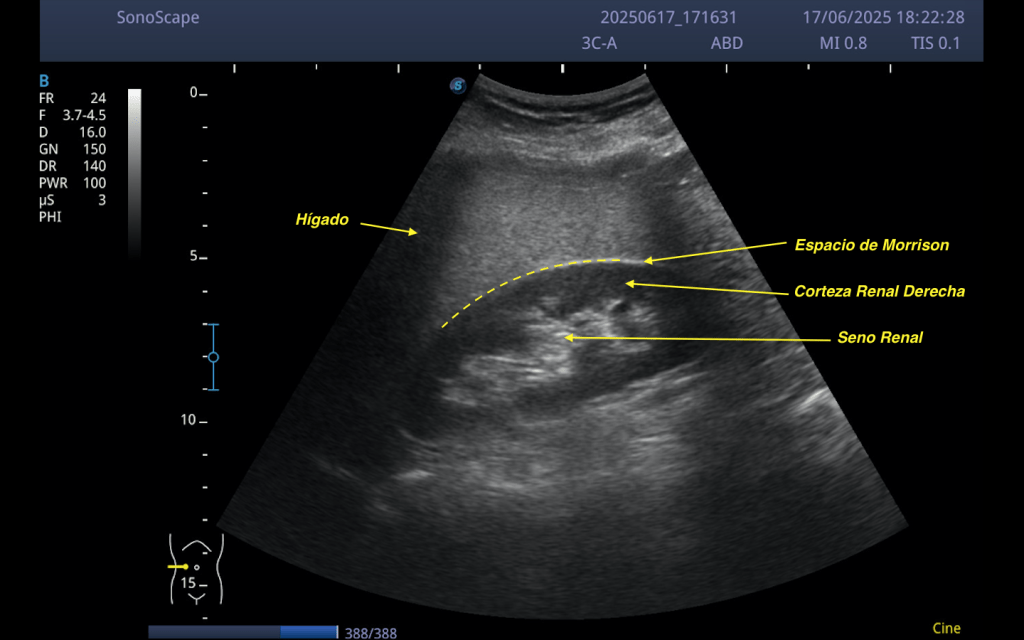

En la imagen se observa un riñón derecho en corte longitudinal, con:

Corteza renal hipoecogénica, de aspecto homogéneo. Seno renal hiperecogénico, bien delimitado. Entre el riñón y el hígado se identifica el espacio de Morrison, marcado con una línea discontinua, que corresponde al receso hepatorrenal.

Este espacio es fundamental no solo en situaciones de trauma o búsqueda de líquido libre, sino también como referencia anatómica para la comparación de parénquimas.

En condiciones normales, el parénquima hepático debe ser isoecogénico o ligeramente más ecogénico que la corteza renal.

El hígado aparece marcadamente hiperecogénico. La corteza renal mantiene una ecogenicidad baja, dentro de la normalidad.

Esta diferencia de ecogenicidad sugiere que no es el riñón el que está alterado, sino el hígado.